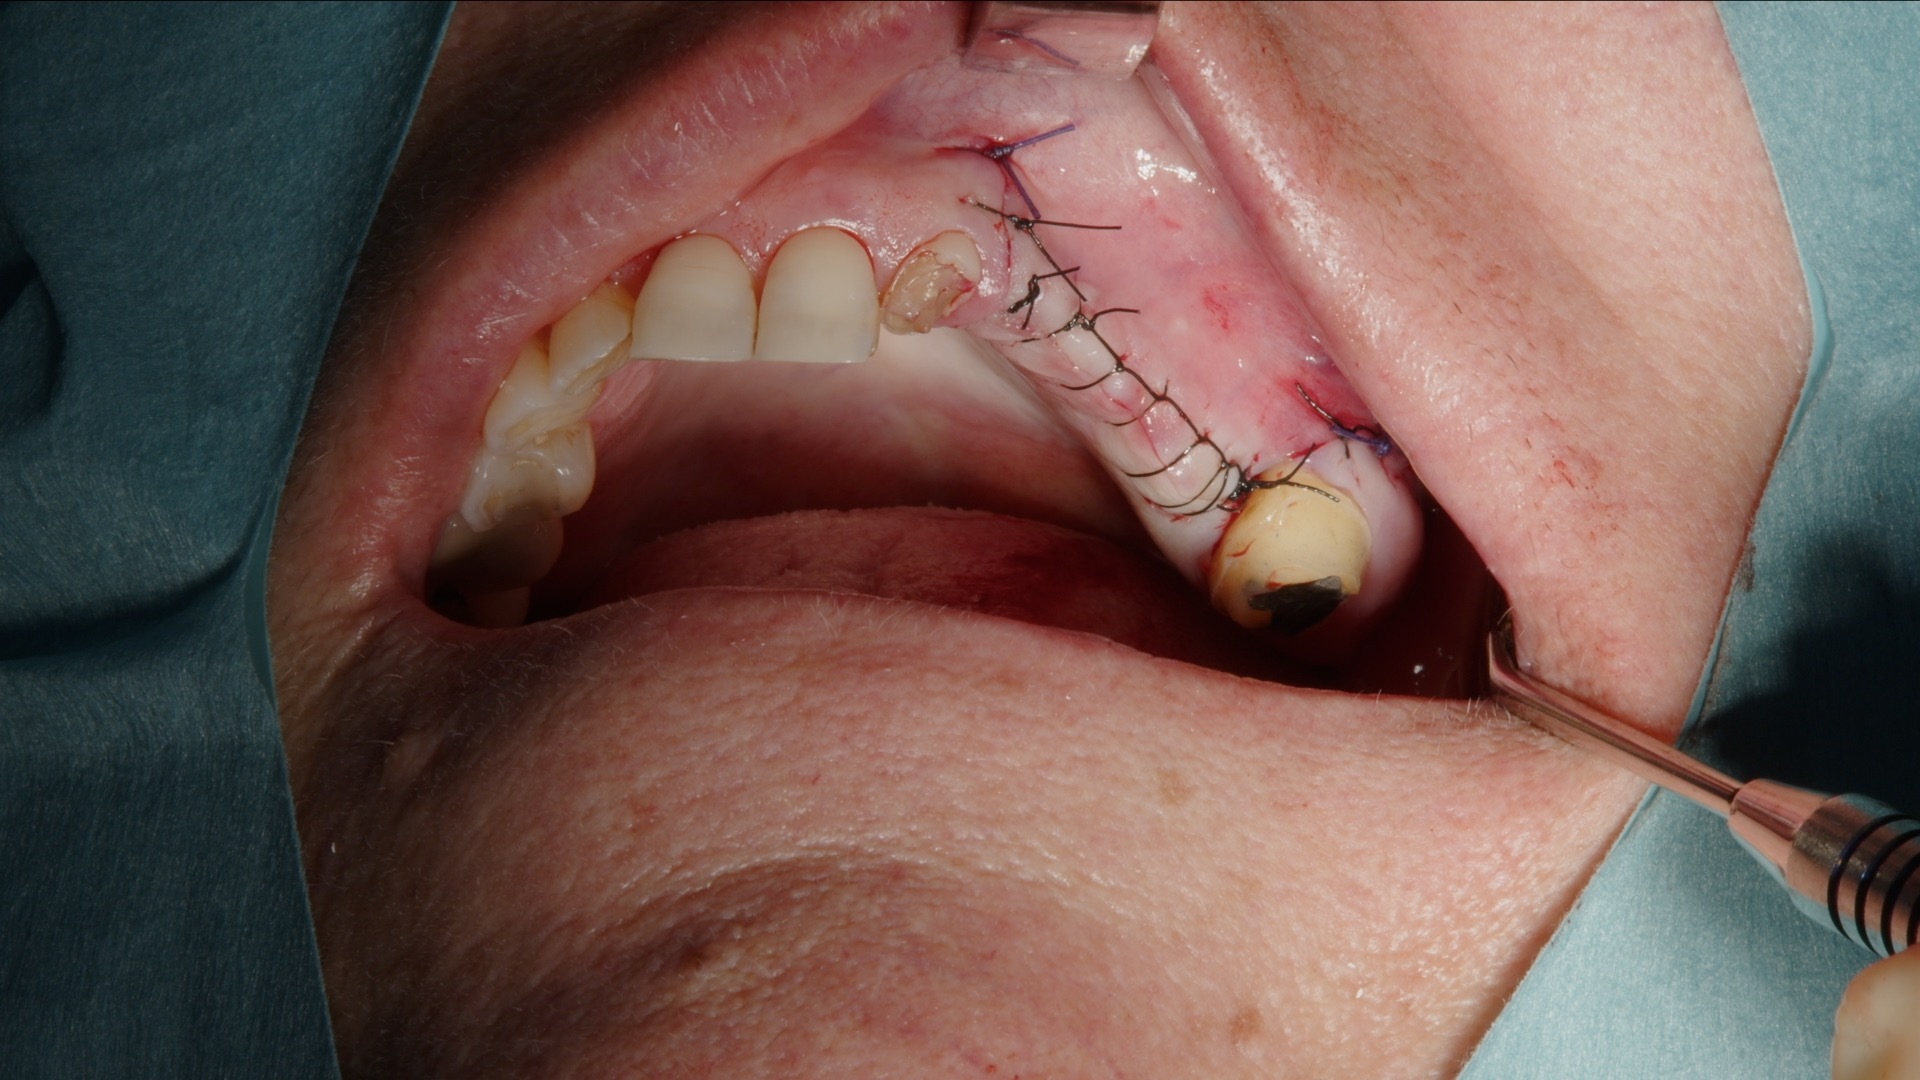

Etter utfylling dekkes det laterale vinduet med Geistlich Bio-Gide kollagenmembran. Membranet fungerer som en barriere mot bløtvevsinnvekst og stabiliserer transplantatet i tilhelingsfasen. Deretter reposisjoneres lappen tensionfritt og sutureres nøye.

8. Suturering av lapp.